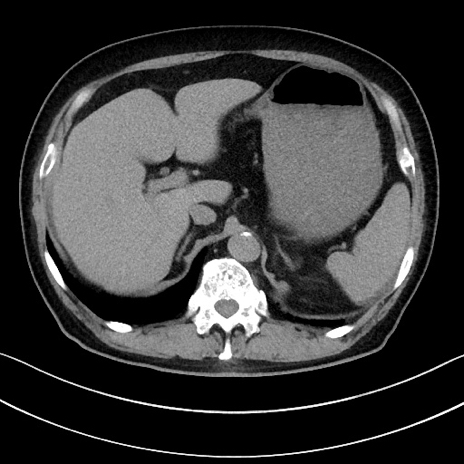

症例15(横断像)

【症例】70歳代男性

【主訴】腹痛

【現病歴】今朝から腹痛あり。全体的に痛い。特に左上の方。排ガスが今日はない。冷や汗が出る。

【既往歴】直腸癌術後

【身体所見】左側腹部〜上腹部に圧痛あり。腹膜刺激症状明らかなではない。軽度反跳痛。左下腹部に術後瘢痕あり。

【データ】WBC 7700、CRP 0.02